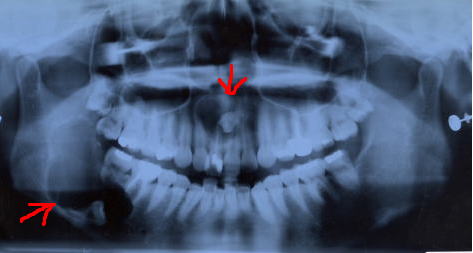

症例1

左下の歯の痛みを主訴にを受診。

その時撮影したパノラマ写真で偶然に、右下顎角部に本疾患の存在が分かりました。

レントゲン像からエナメル上皮種を疑いました。

即日、大学医学部歯科口腔外科に治療依頼の紹介をしました。

右下顎臼歯から、角部、枝部にかけて透過像があります。また上顎の前歯部には含歯性嚢胞も認められます。